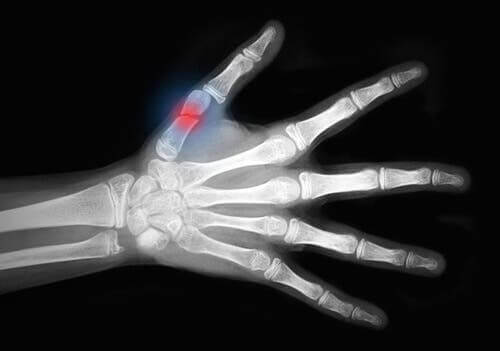

Tot slot zijn er Graad III-verwondingen. Huidavulsies ontstaan bij de ernstigste groep verwondingen aan zacht weefsel. Deze verwondingen gaan gepaard met ernstige huid- en spierschade, zoals:

- vasculaire schade.

- acuut compartimentsyndroom. Dit is een ernstige aandoening waarbij de druk in een spiercompartiment ernstig verhoogd is. Het kan leiden tot zenuw- en spierschade, evenals problemen met de doorbloeding.

- beknellingsletsel.

- huidavulsies.

- Herimplantatie. Dit bestaat uit het terugplaatsen van lichaamsdelen die zijn geamputeerd. Denk bijvoorbeeld aan de vingers van een hand.